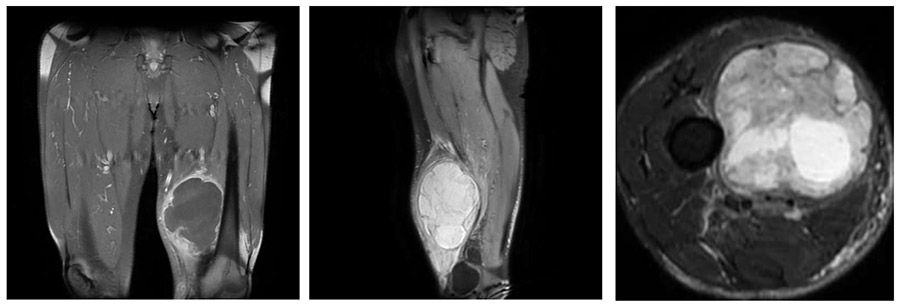

Ameliyat Öncesi: Kitlenin MR’da femur kemiğine ve damar-sinir paketine bitişik düzensiz sınırlı, heterojen görünümü